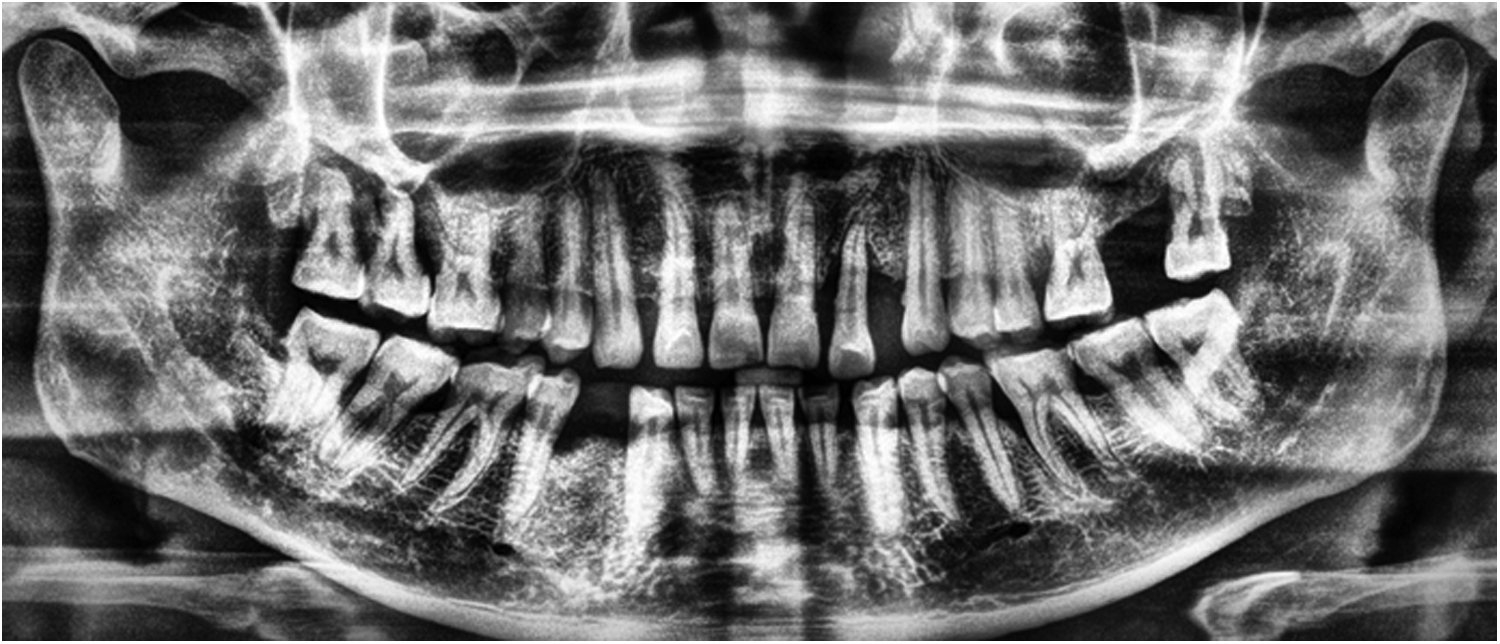

Image Sharpening: Enhancing edges to make pixel boundaries more distinct and improve visual interpretability (Figure 1).

Figure 1

An illustration of image sharpening: (A) represents original image, and (B) represents sharpened image.